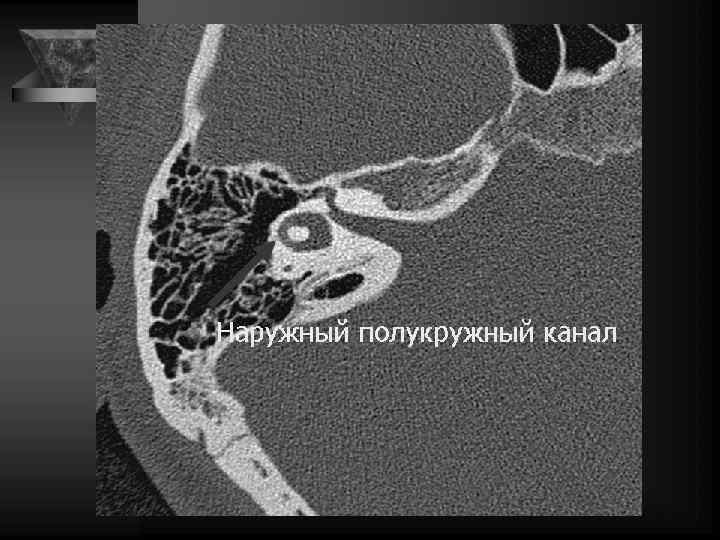

Внутреннее ухо и верхушка пирамиды • Улитка: деминерал-я костной капсулы, спирал-й канал улитки и его просвет, оссификация • Преддверие и полукружные каналы, интактные стенки, оссификация • Внутр. слух. проход: расширение, неровн-ть контура, деструкция кости, стеноз • Канал лицев. нерва до коленч. ганглия. • Водопровод преддв-я и водопр. улитки. • Верхушка пирамиды: губчатая или пневматизирована, наличие секрета, наличие образований